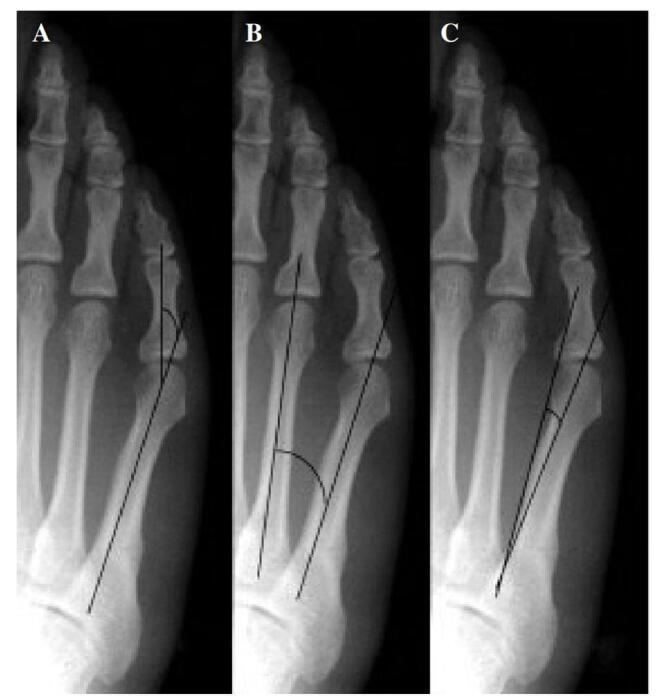

Our systematic review analyzed 26 studies with 8514 participants. Young age was a risk factor in four studies, and female gender in one. High body mass index, increased training hours, competitions, and intense preseason training also raised risk. Anatomical factors included lower calcaneal pitch angle, wider medial malleolar slip angle, higher Talocalcaneal angle, and lower limb varus malalignment. Stress fractures were higher among midfielders in one study, while two others found no positional differences. Additional risks were elevated parathyroid hormone, higher bone-specific alkaline phosphatase, lower 25OH levels, fasting, and perceived stress from negative life events.

我们的系统评价分析了26项研究,涉及8514名参与者。四项研究表明年龄小是一个风险因素,一项研究表明女性是风险因素。高体重指数、训练时间增加、比赛次数和季前强化训练也会增加风险。解剖学因素包括跟骨倾斜角较低、内踝滑动角较宽、距跟角较高以及下肢内翻畸形。一项研究表明中场球员应力性骨折发生率较高,而另外两项研究未发现位置差异。其他风险因素包括甲状旁腺激素升高、骨特异性碱性磷酸酶水平较高、25OH水平较低、禁食以及负面生活事件带来的感知压力。